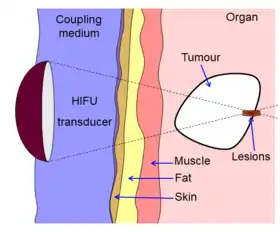

Diagram showing how HIFU can be used to destroy tissue in the body. An acoustic lens is used to focus sound to a small point in the body. The sound propagates through many layers of tissue. Because of the focal gain, only tissue at the focus is destroyed. | |

High-intensity focused ultrasound (HIFU) is a non-invasive therapeutic technique[1] that uses non-ionizing ultrasonic waves to heat or ablate tissue. HIFU can be used to increase the flow of blood or lymph or to destroy tissue, such as tumors, via thermal and mechanical mechanisms. Given the prevalence and relatively low cost of ultrasound generation mechanisms, the premise of HIFU is that it is expected to be a non-invasive and low-cost therapy that can at least outperform care in the operating room.

The technology is different from that used in ultrasonic imaging, though lower frequencies and continuous, rather than pulsed, waves are used to achieve the necessary thermal doses. However, pulsed waves may also be used if mechanical rather than thermal damage is desired. Acoustic lenses are often used to achieve the necessary intensity at the target tissue without damaging the surrounding tissue. The ideal pattern diagram is the beam-focusing of a magnifying glass of sunlight; only the focal point of the magnifying glass has high temperature.

HIFU beams are precisely focused on a small region of diseased tissue to locally deposit high levels of energy.

Beam delivery

Beam delivery consists of beam steering and image guidance. The beam has the ability to pass through overlying tissues without harm and focus on a localized area with size limit of 2-3 mm, that is determined the clinical frequency of the ultrasound. Following ablation a distinct boundary forms between healthy and necrotic tissue (width less than 50 microns).[31]